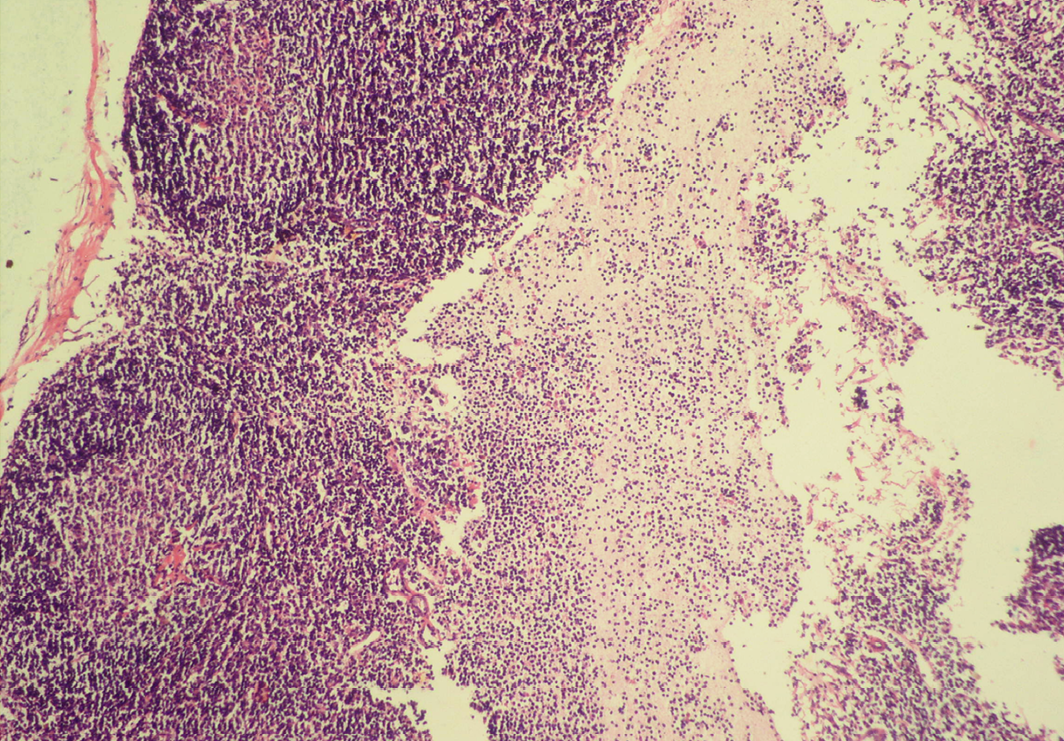

Reactive hyperplasia in mesenteric lymph node

In cortex, number of follicles is increased and also showing increased number of lymphocytes; H&E x100

Depletion of follicles in the cortex and medulla

Sheet of inflammatory cells are present over homogenous meshwork of fibrin strands; H&E x100